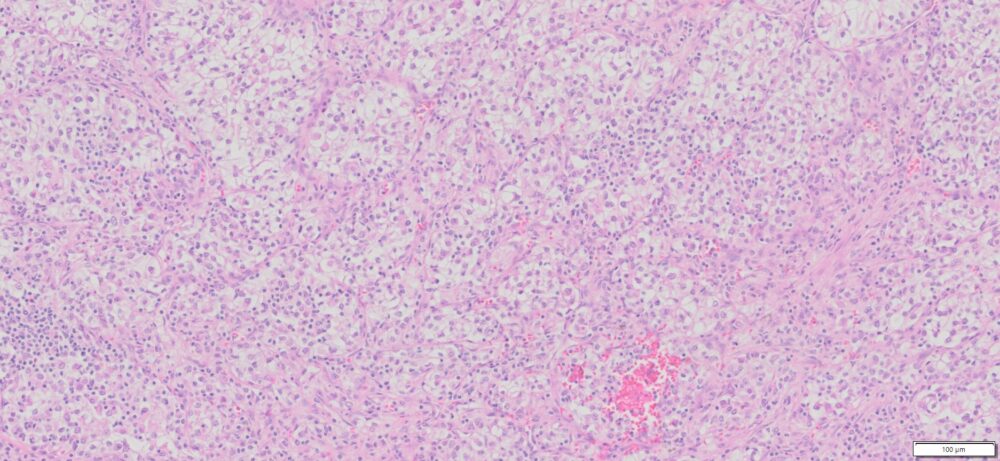

| HuPS-05001T1 | Kidney | Clear –cell renal cell carcinoma | No | Male/63 | 80% | II/III | pT3N1Mx | NA |

Human tissue was fixed in formalin immediately after excision and embedded in paraffin. The tissue sections were 5 µm in thickness and mounted each on positively charged glass slides.